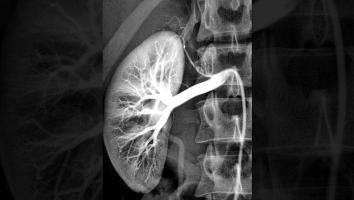

De meeste mensen hebben twee werkende nieren. Ze zitten links- en rechtsonder in je rug, tegen je ruggengraat aan en zijn ongeveer zo groot als een vuist bij volwassenen. In principe heb je er maar één nodig om gezond te blijven.

Nieren houden je bloed schoon. Ze verwijderen afvalstoffen uit je lichaam die je bijvoorbeeld binnenkrijgt via je eten of medicijnen. Een nier bestaat uit miljoenen kleine filtertjes waar ieder uur zo'n 60 liter bloed doorheen stroomt. De filters in je nieren vangen de schadelijke stoffen in het bloed op en sturen het afval vervolgens in de vorm van urine naar je blaas. Via die weg plas je dus de afvalstoffen uit. Het gefilterde bloed geven je nieren weer terug aan je lichaam.